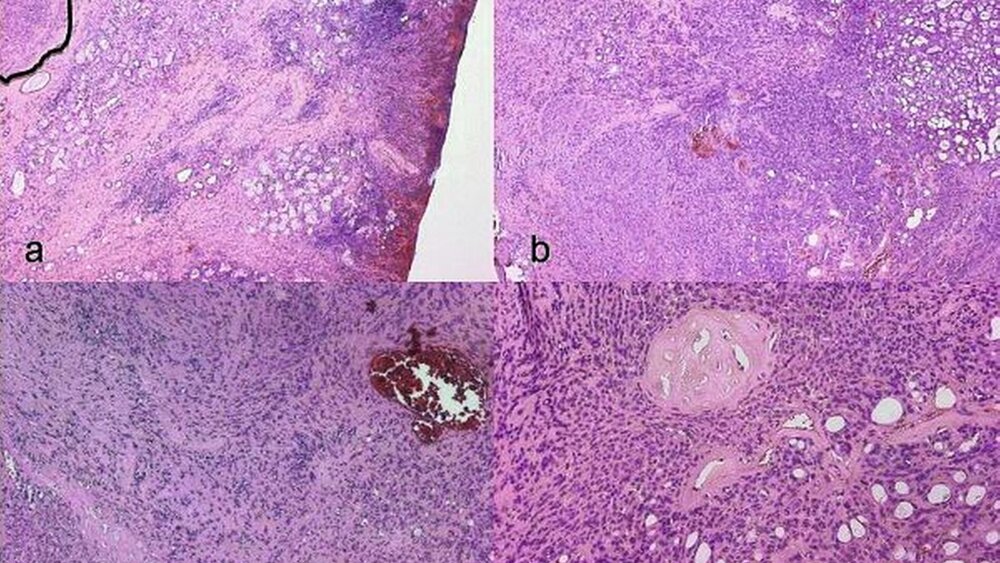

Das abschließende histo-pathologische Gutachten diagnostizierte mittels immunhistochemischer Zusatzuntersuchungen ein pleomorphes Adenom der kleinen Speicheldrüsen ohne Anhalt für Malignität (Abbildung 4).

Histopathologisch ist das pleomorphe Adenom durch eine strukturelle Pleomorphie aus epithelialen und myoepithelialen Zellen gemischt mit mukoidem, myxoidem oder chondroidem Stroma gekennzeichnet [Eveson et al. 2005]. Je nach überwiegendem Stromaanteil weisen die Tumoren daher eine eher derbe oder weiche Konsistenz auf. Letzteres hatten die Kollegen bei der Patientin an eine „Speichelzyste“ denken lassen.